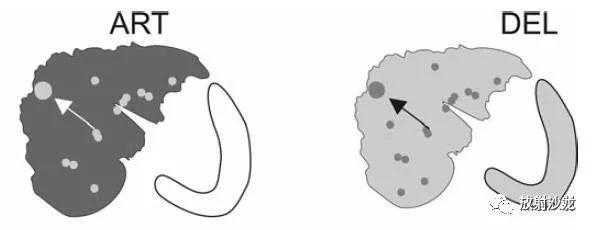

(1)DN中出现局部脂肪浸润,结合甲胎蛋白(AFP)缓慢升高,提示其逐渐演变为HCC;

(2)T2WI上在DN结节内出现高信号,提示演变为HCC;

(3)出现明显的新生血管。

DN-HCC转变,MRI表现:

A~D:影像表现如上所述。12个月后复查:

E:T2压脂未见明确病灶;

F:同反相位示病灶体积增大,反相位呈低信号;

G:动脉期,结节有强化;

H:延迟期,结节内造影剂廓清,提示其为DN并局灶性HCC。